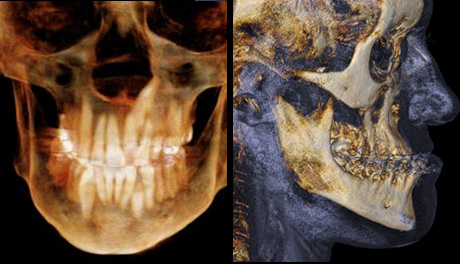

Cone-Beam Computed Tomography (CBCT) is an advanced 3D imaging modality that plays a transformative role in treatment planning. When properly acquired and systematically analyzed, CBCT data significantly enhances patient care. It is essential for clinicians to evaluate all anatomical structures captured in the scan, rather than focusing solely on the region of interest. A comprehensive interpretation of the entire dataset is critical for developing an accurate and effective treatment plan.

At Voxel Readers, we are a team of skilled, dedicated professionals devoted to extracting the maximum clinical value from your scans. We provide the highest quality CBCT data interpretation and support, ensuring timely, professional analysis to guide your decision-making process. Our secure, web-based platform is intuitive, user-friendly, and mobile-enabled. Once files are uploaded to our secure server, we analyze the data and provide a detailed report, including relevant images in PDF format. You will be promptly notified via email once the report is ready. Our interpretation services are completed within 3–4 business days.

Voxel Readers is committed to delivering an exhaustive analysis of your scan data, empowering you to create the most appropriate treatment plan and ultimately enhancing the quality of care you provide to your patients.